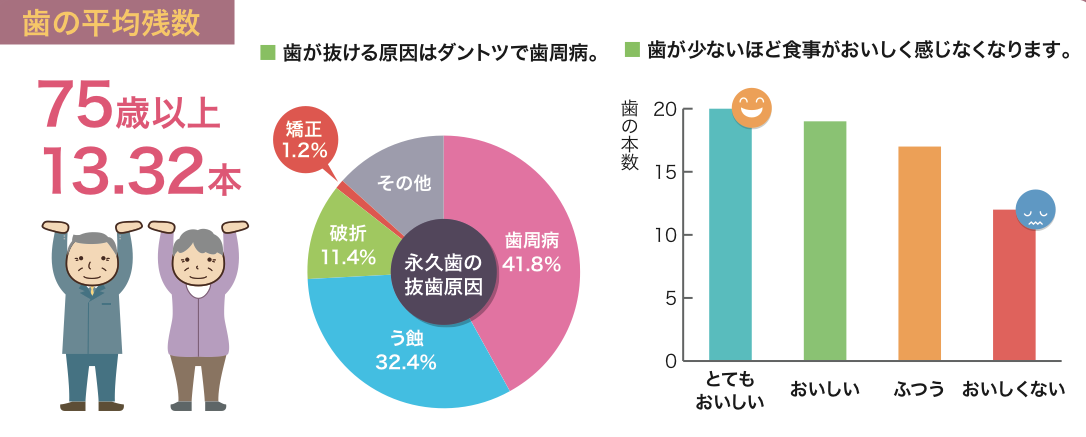

日本人の歯を失う原因の第2位が虫歯です

日本人の歯が残っている本数はどうなっているのでしょう

答えは・・・・

なんと75歳で歯が残っているのは

平均13.32本

自分の歯は全部で28本あります

(親しらずを入れると32本あります)